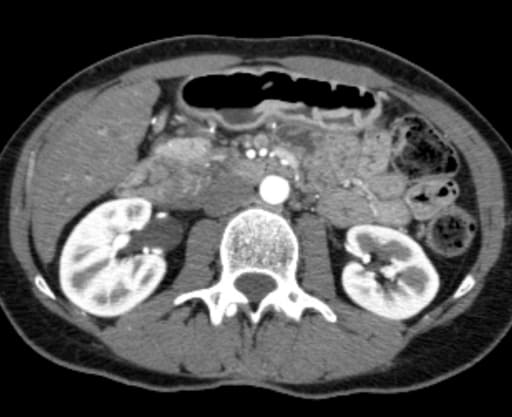

Инструментальные методы диагностики синдрома культи пузырного протока включают в себя следующие обследования:

- чрескожная чреспеченочная холангиография (ЧЧС);

- эндоскопическая ретроградная холангиопанкреатография (ЭРХПГ);

- МРТ-холангиография;